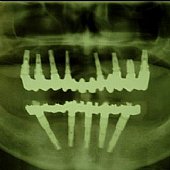

• Röntgendarstellung der implantatgetragenen Vollkeramikbrücke im Oberkiefer und klassische Versorgung des zahnlosen Unterkiefers nach der Branemark-Methode.